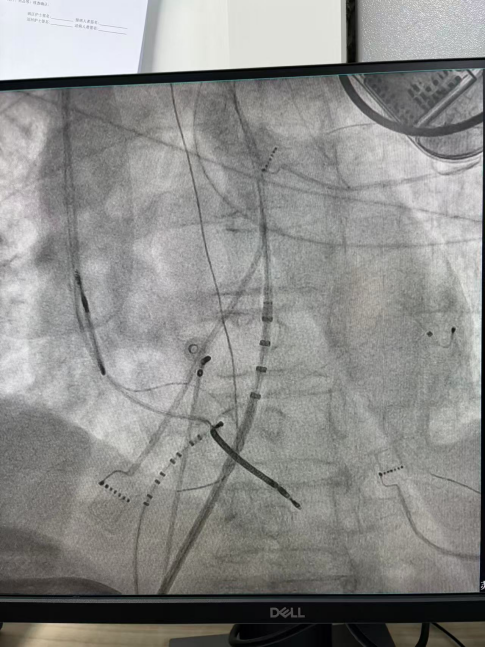

干穿心包进入外膜标测

王林林主任医师谨慎操作,成功进入心外膜达到病变位置。术中,患者反复自发多形态室速,且转为室扑,同时出现血流动力学不稳定,需多次电除颤方能终止发作,标测难度极大。这就要求医疗团队必须在有限的标测时间内精准定位室速消融靶点,并结合心内外膜基质特征制定消融策略。经针对性消融后,患者未再自发室速,且室性早搏转为单一形态,经判定为右心室乳头肌来源,随即予以一并消融。术后经心室程序电刺激验证,室速未再被诱发。